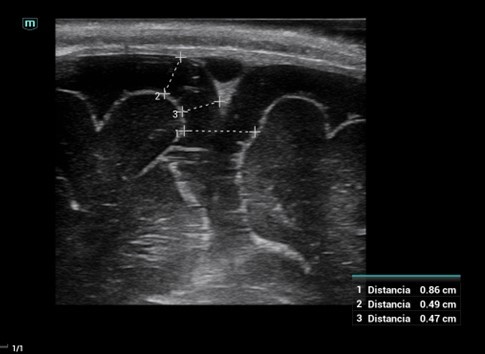

Se debe realizar la ecografía con una sonda lineal de alta frecuencia a través de la fontanela anterior. Se debe medir la amplitud del espacio subaracnoideo en el plano coronal, a la altura del agujero de Monro. Las medidas más utilizadas son la amplitud interhemisférica (1), la distancia entre la tabla interna y la corteza cerebral (2) y entre el seno venoso y la cortical (3) (Figura 1). No existe un claro consenso sobre el rango normal de valores. Sus amplitudes varían con la edad, pero por encima de 10 mm son siempre patológicas.

Figura 1. Ecografía